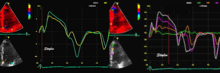

Colour tissue Doppler

Unlike spectral Doppler, Colour tissue Doppler samples velocities from all points of the sector, by shooting two pulses successively, and calculating the velocity from the phase shift between them by autocorrelation. The calculation is slightly different from the true Doppler effect, but the result becomes identical. This results in a single velocity value per sample volume. The result is a velocity field of (nearly) simultaneous velocity vectors towards the probe. The advantage of colour Doppler over spectral Doppler is that all velocities can be sampled simultaneously. The disadvantage is that if there is clutter noise (stationary reverberations), the stationary echoes will be integrated in the velocity calculation, resulting in an under estimate. As pulsed wave Doppler are displayed as a spectrum, the colour Doppler values will correspond to the mean of the spectrum (in the absence of clutter), giving slightly lower values. In the HUNT study, the difference in peak systolic values were about 1.5 cm/s.[26]

The local velocities are not the result of the local function, as segments are moved by the action of neighbouring segments. Thus the velocity differences velocity gradient are the main measure of regional contraction, and has become the most important employment of colour tissue Doppler, in the method of strain rate imaging.[27]